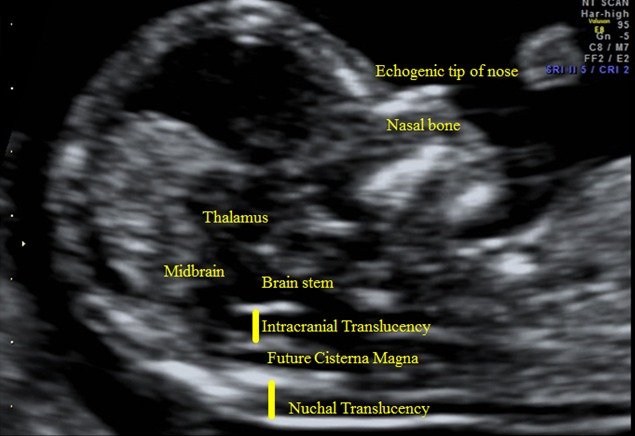

The NT scan (Nuchal Translucency scan) is a specialised ultrasound performed in early part of pregnancy to assess the baby’s risk for certain chromosomal and structural conditions.

It measures a small fluid-filled space at the back of the baby’s neck called Nuchal Translucency. Increased thickness in this area can be associated with chromosomal conditions or certain structural abnormalities.

- Nuchal translucency thickness

- Presence of nasal bone

- Baby’s heart rate and tricuspid flow

- Ductus Venosus flow